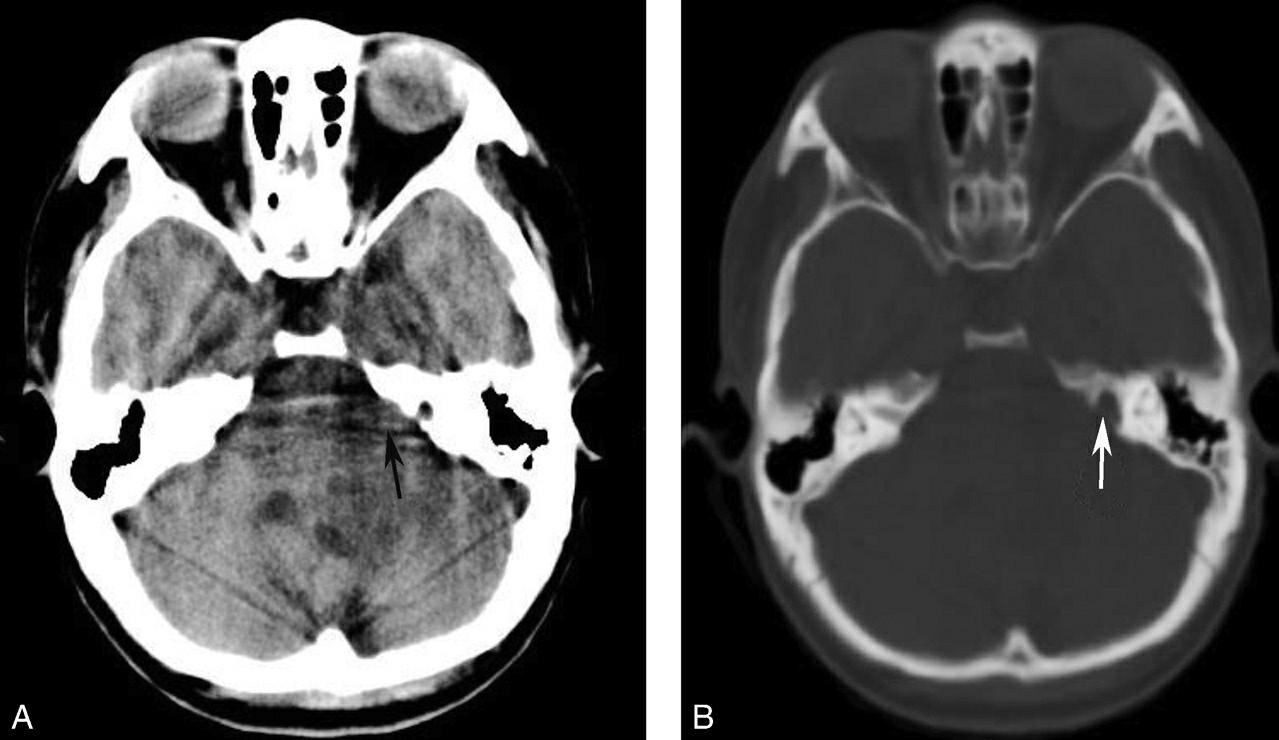

破裂孔、卵圆孔、棘孔及斜坡等均为重要的解剖结构,临床常见疾病如鼻咽癌常侵犯上述结构(图1-2-3)。颈静脉孔区较常见的肿瘤为颈静脉球瘤,常伴有颈静脉孔及其邻近骨质的破坏(图1-2-4)。

图1-2-3 鼻咽癌颅底骨质破坏

A.横断面;B.横断面(骨窗)

骨窗示左侧岩尖、斜坡、左侧蝶骨大翼骨质破坏、受侵(白箭),肿瘤经破裂孔侵入颅内(黑箭头)

图1-2-4 右侧颈静脉球瘤

A.横断面(骨窗);B.横断面

右侧颈静脉孔区不规则骨质破坏(箭),局部见软组织肿块(☆)